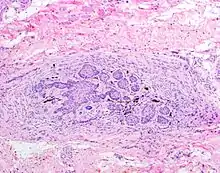

The juxtaoral organ of Chievitz is composed of nests of benign squamoid epithelium closely associated with multiple nerve bundles. The deep location and squamous appearance can histologically mimic invasive squamous cell carcinoma. (Hematoxylin and Eosin stained section, 100x magnification) | |

The juxtaoral organ in humans is a small longish structure (10–14 mm in length, 1–2 mm in diameter), situated medially to the medial pterygoid muscle. The organ consists of a central ramified cord of epithelial parenchyma, embedded in connective tissue particularly rich in nerve fibers and sensory receptors. Close relations exist between epithelial cells and nerve endings. Histochemically, the parenchyma displays a characteristic pattern of various enzymes. Sporadically, epithelial follicles containing colloidal material can be found. The organ is surrounded by a dense, perineurium-like connective tissue.